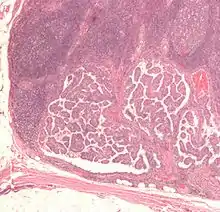

Патогістологічна характеристика

За гістологічними характеристиками визначають класичний папілярний рак, фолікулярний варіант папілярного раку, дифузносклеротичний варіант, веретеноклітинний варіант, інкапсульований неінвазивний варіант папілярного раку.

- Характерним для папілярного раку є наявність нуклеарних включень (ядро клітини, при фарбуванні гематоксиліном-еозином, містить порожні ділянки)[13] та псамомних тілець при світловій мікроскопії. Ці ознаки використовують при ідентифікації фолікулярного варіанту папілярного раку, при якому клітини не утворюють характерних папілярних структур.[14]